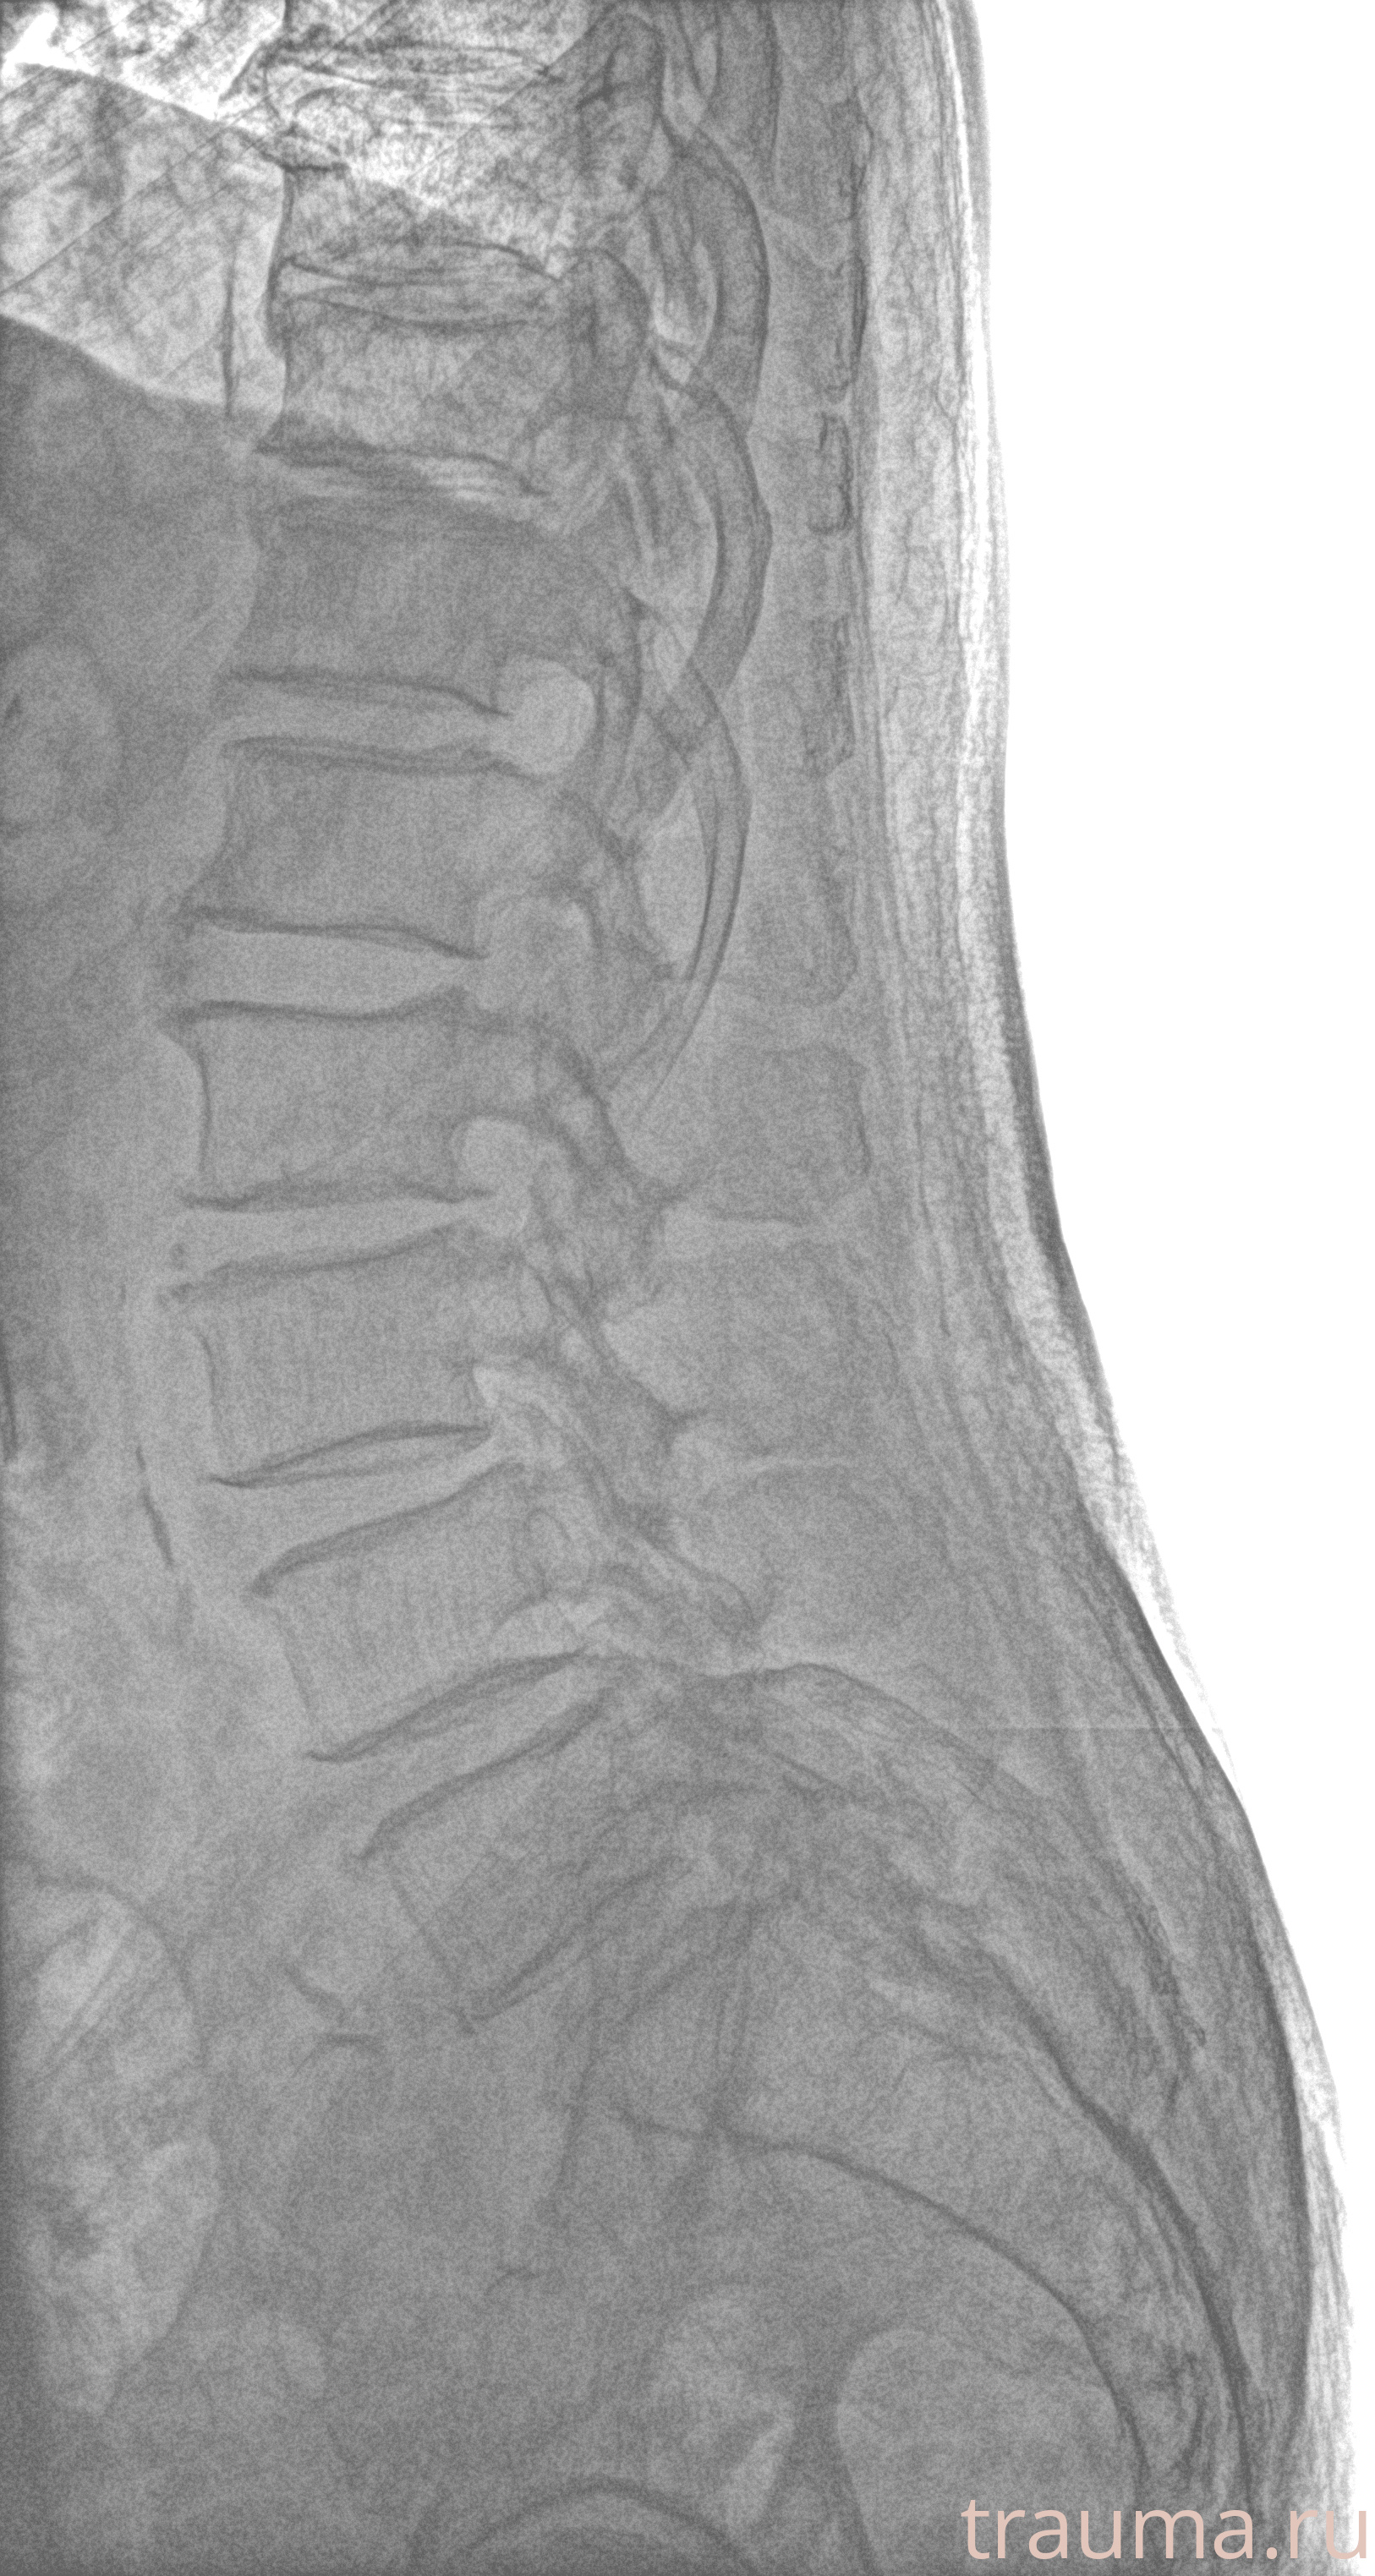

Рентген на дому: по вашему адресу приезжает врач-рентгенолог, травматолог-ортопед с мобильным рентгеновским аппаратом, проводит диагностику травмы или заболевания, делает необходимые рентгенограммы, дает рекомендации по дальнейшему лечению. Получить качественные снимки в домашних условиях возможно благодаря уникальной методике, разработанной МосРентген Центром для института  Склифосовского